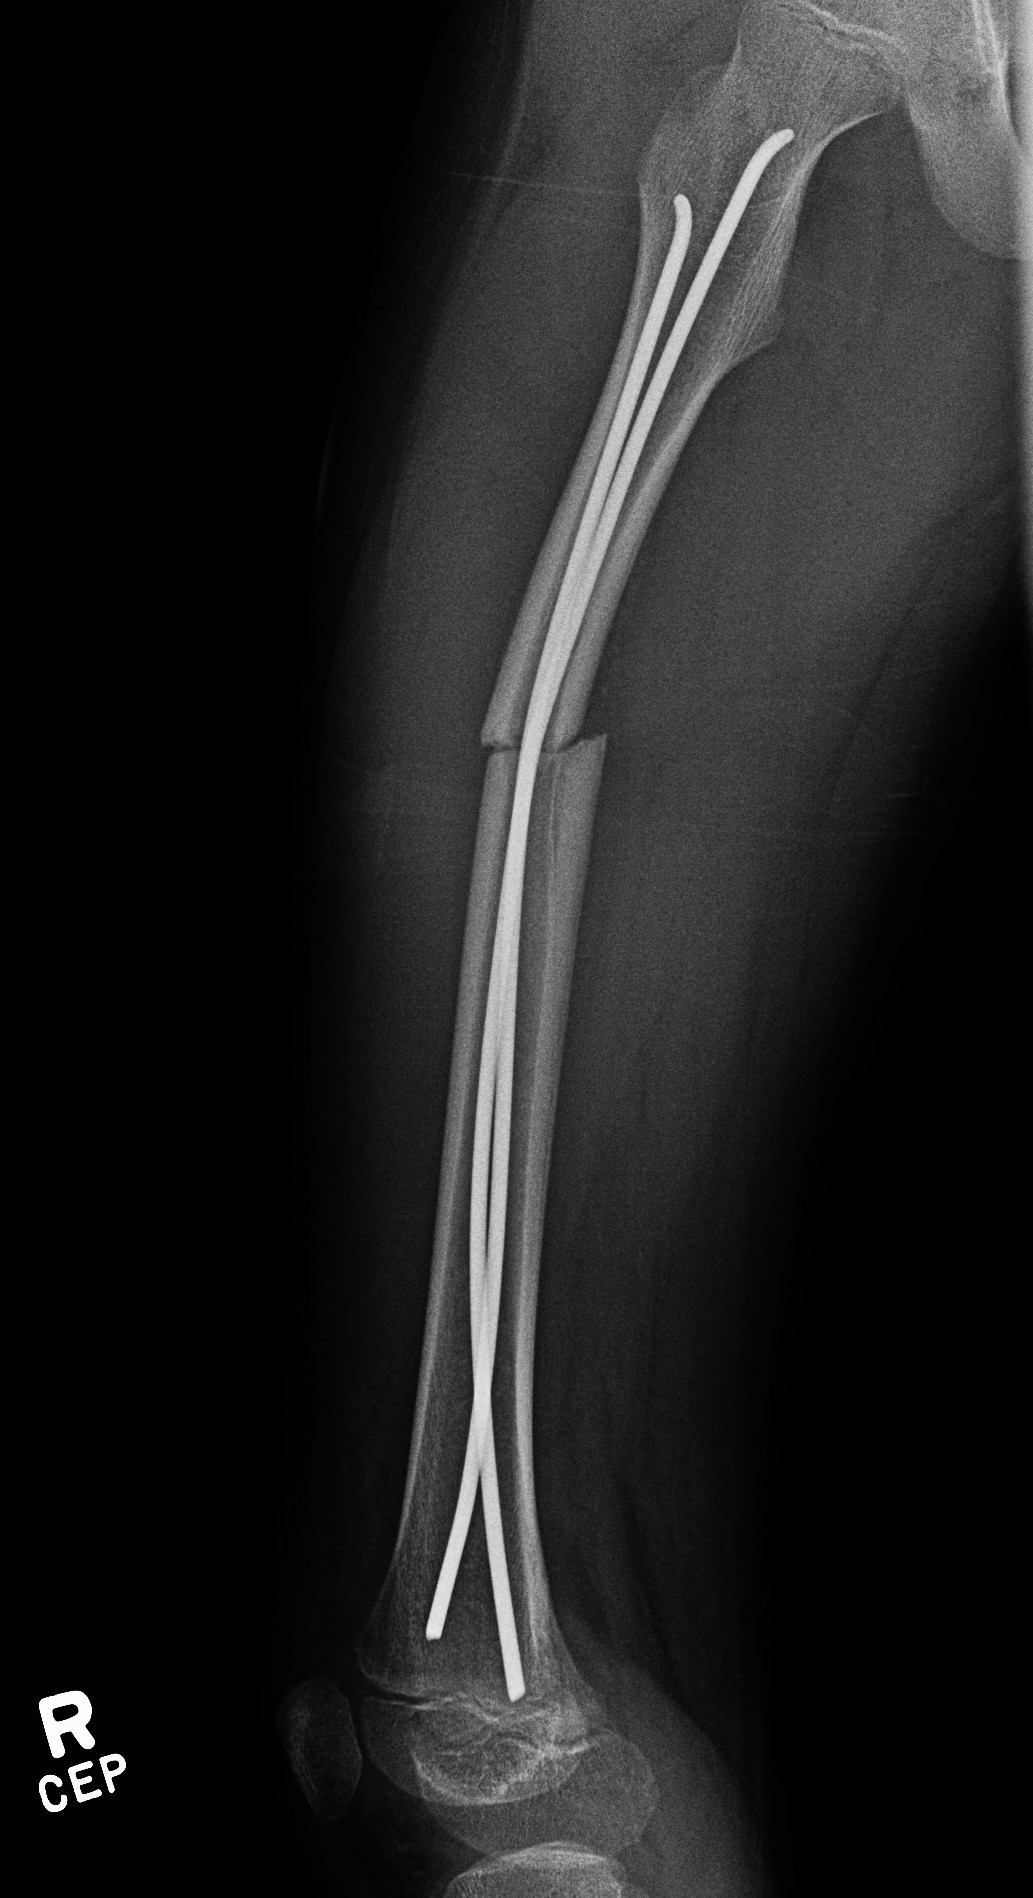

Flexible nails / Titantium Elastic Nails

Indications

Length stable fractures i.e simple transverse, short oblique

Midshaft fractures

Maximum weight up to 50 kg / 12 years old

Flexible nail technique

Wires

- available 1. 5 mm - 4.0 mm

- 30 - 40% of diameter of diaphyseal medullary canal

- i.e. if canal 10 mm wide, use 2 x 4 mm

- recommend using 2 wires same diameter to avoid rotational instability

Entry points

- medial and lateral insertion

- 1 - 2 cm proximal to distal femoral physis

- oblique entry with awl in direction of nail insertion

- can open with drill bit

- beware proximity of the femoral artery medially

- entry points should be symmetrical

Wire passage

- bend wire for 3 point fixation with bend at fracture site

- also bend the tip of the wire

- can use F Tool to reduce fracture / sheet in groin

- may need small incision and open reduction

- medial entry wire will pass into femoral neck

- lateral wire will pass into greater trochanter / medial wire into femoral neck

- use designated TEN wire cutter to cut wires

- cut off, tap in slightly further, leave 1.5 cm out so can retrieve

- wires that are too prominent can cause bursa / limit flexion / pain / protrude through skin

Acceptable alignment

- 10o varus / valgus

- 15o flexion / extension

- 15 mm shortening